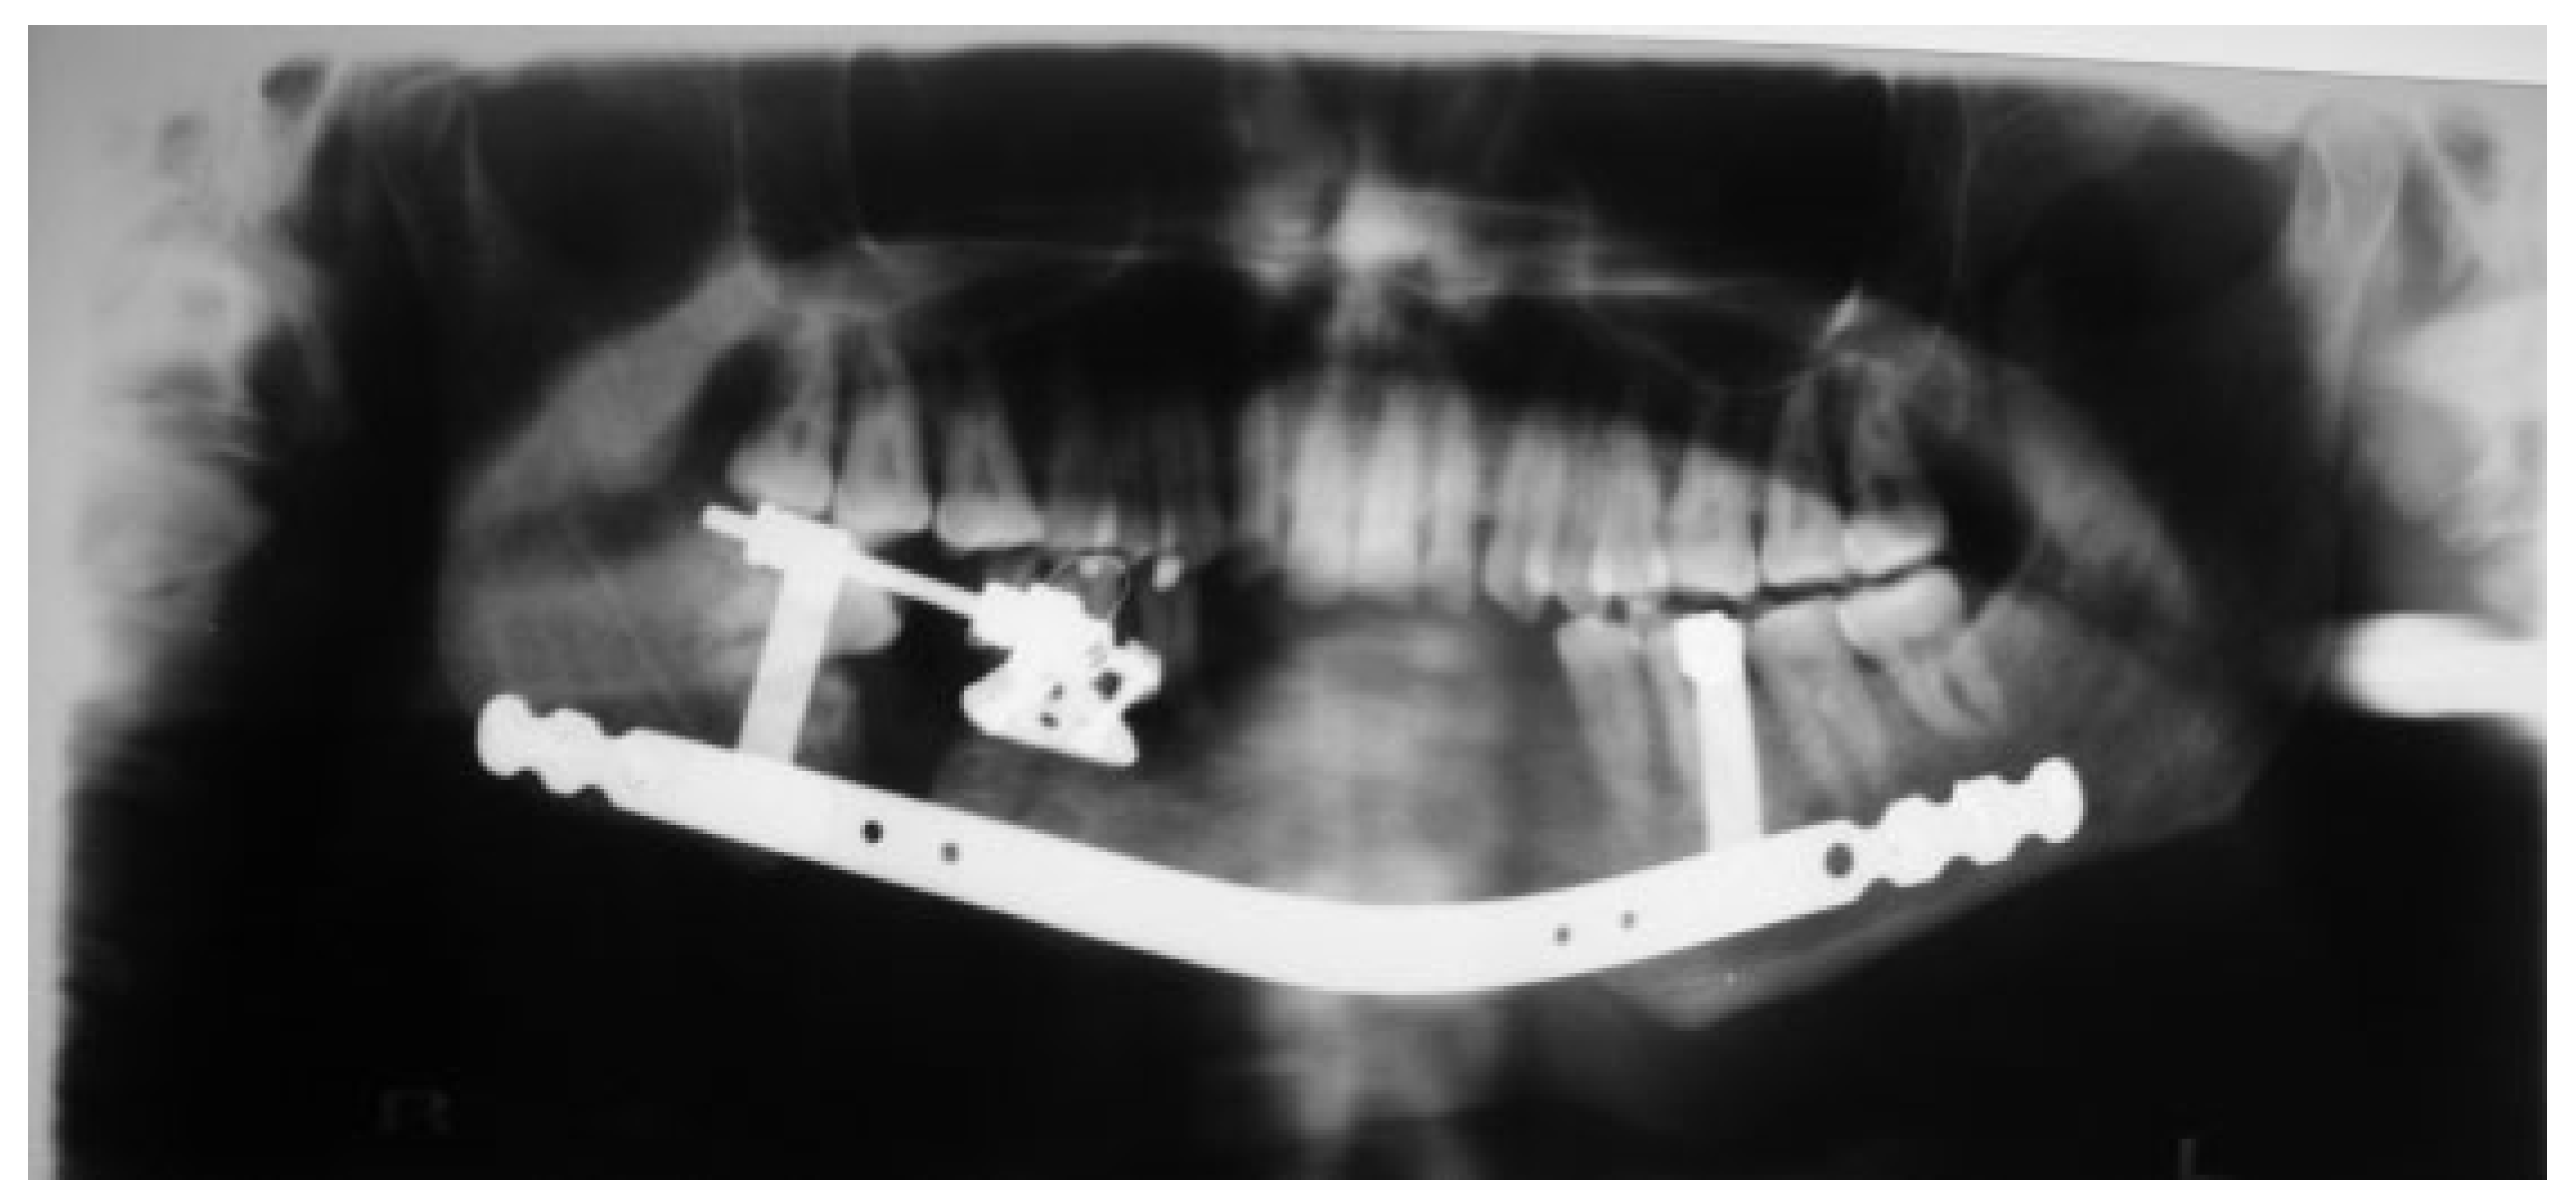

Figure 10.

An orthopantomogram view showing the extent of the defect in case 2 along with an attempt to reconstruct using a reconstruction plate.